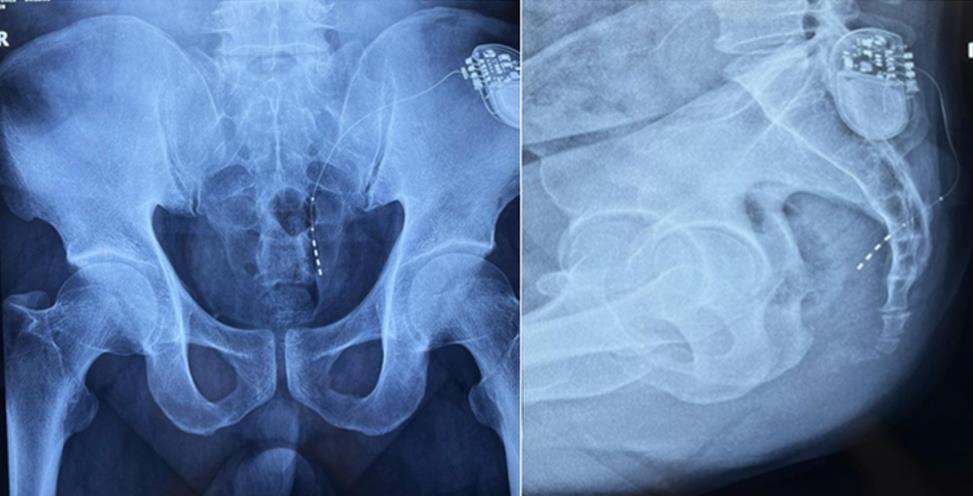

該患者兩年前被診斷患有膀胱過度活動癥(OAB),出現嚴重尿頻、尿急、尿細線等癥狀,醫(yī)生為其做了骶神經調控手術。近期,患者癥狀又開始加重,生活質量受到影響,為減輕癥狀,改善生活,患者前往南醫(yī)大二附院就診。衛(wèi)中慶主任及其團隊在查看患者病情后,決定重新調整電極刺激位置,將刺激點由原左側骶4神經孔改為骶3神經孔,通過新的神經調節(jié)順利地改善了癥狀。

患者術前影像

大平板一體式移動C形臂術中影像

在骶神經調控術或者骶神經刺激術(SNS)中,醫(yī)師首先會在透視引導下把電極通過導針插入到骶3神經孔位置,通過脈沖電流的刺激,達到興奮神經纖維并抑制逼尿肌收縮。在這一步,醫(yī)師會先對患者的神經刺激反應做測試評估,如果刺激效果明顯,說明該方案能夠達到手術預期。接下來醫(yī)師會在附近皮下脂肪處植入一塊脈沖電流發(fā)生器并與電極相連,使該部位今后能得到長期的電刺激,改善OAB癥狀。